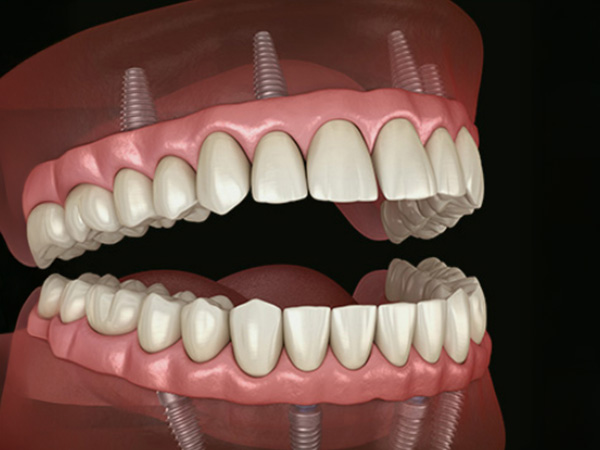

무절개 임플란트틀니는 잇몸을 크게 절개하지 않고, 잇몸 표면에 작은 구멍을 내어 임플란트 고정체를 심은 뒤 그 위에 틀니가 단단히 연결되도록 설계하는 치료입니다. 이 방법은 기존 틀니에 비해 잘 빠지지 않고 덜 흔들려, 식사나 대화 시 안정감 있는 사용을 돕는 것을 목표로 합니다.

잇몸을 넓게 여는 수술에 비해 시술 시간이 짧고 부기와 통증이 적어 고령의 환자분이나 전신질환이 있는 분들도 비교적 부담을 줄이고 치료를 계획하실 수 있습니다. 충분한 검사와 상담을 통해 잇몸 뼈 상태를 확인한 후 개인별로 임플란트 개수와 위치를 조절해, 일상생활에 무리가 적도록 기능과 편안함을 함께 고려하여 진행합니다.